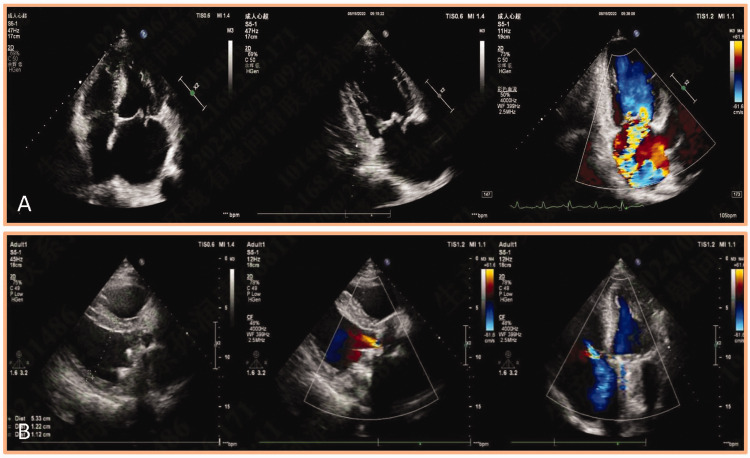

Human parvovirus B19 infection in immunocompetent adults predominantly manifests as arthropathy or erythema infectiosum, with transient aplastic crisis being a rare hematological complication. We report a diagnostically challenging case of a man in his late 40s who developed recurrent severe aplastic anemia following mechanical valve replacement. Notably, the patient presented with progressive pancytopenia despite optimal anticoagulation and normally functioning prosthetic valves on serial echocardiograms. Critical diagnostic differentiation was achieved through comprehensive laboratory evaluation; elevated lactate dehydrogenase (232.00 U/L) and undetectable haptoglobin levels initially suggested mechanical hemolysis. However, suppressed reticulocyte production index (0.002) and the presence of human parvovirus B19 (DNA) confirmed virus-mediated marrow suppression. The absence of schistocytes on peripheral smear and stable hemoglobinuria levels further excluded prosthetic valve-related hemolysis. To the best of our knowledge, this study represents the first documented case of human parvovirus B19-induced aplastic anemia in a postcardiotomy patient with confirmed valve competence, highlighting three key clinical imperatives: 1. Human parvovirus B19 should be included in the differential diagnosis of postoperative pancytopenia regardless of immune status; 2. disproportionate reticulocytopenia with normal hemolysis markers may indicate viral marrow infiltration; and 3. serial echocardiographic surveillance cannot fully exclude subclinical hemolysis, necessitating multimodal laboratory correlation.